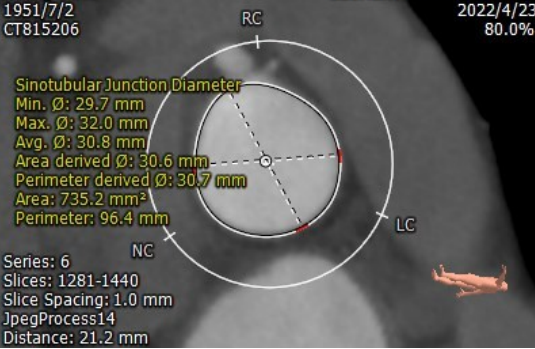

窦管交界处

周长:96.4mm

直径:30.8mm